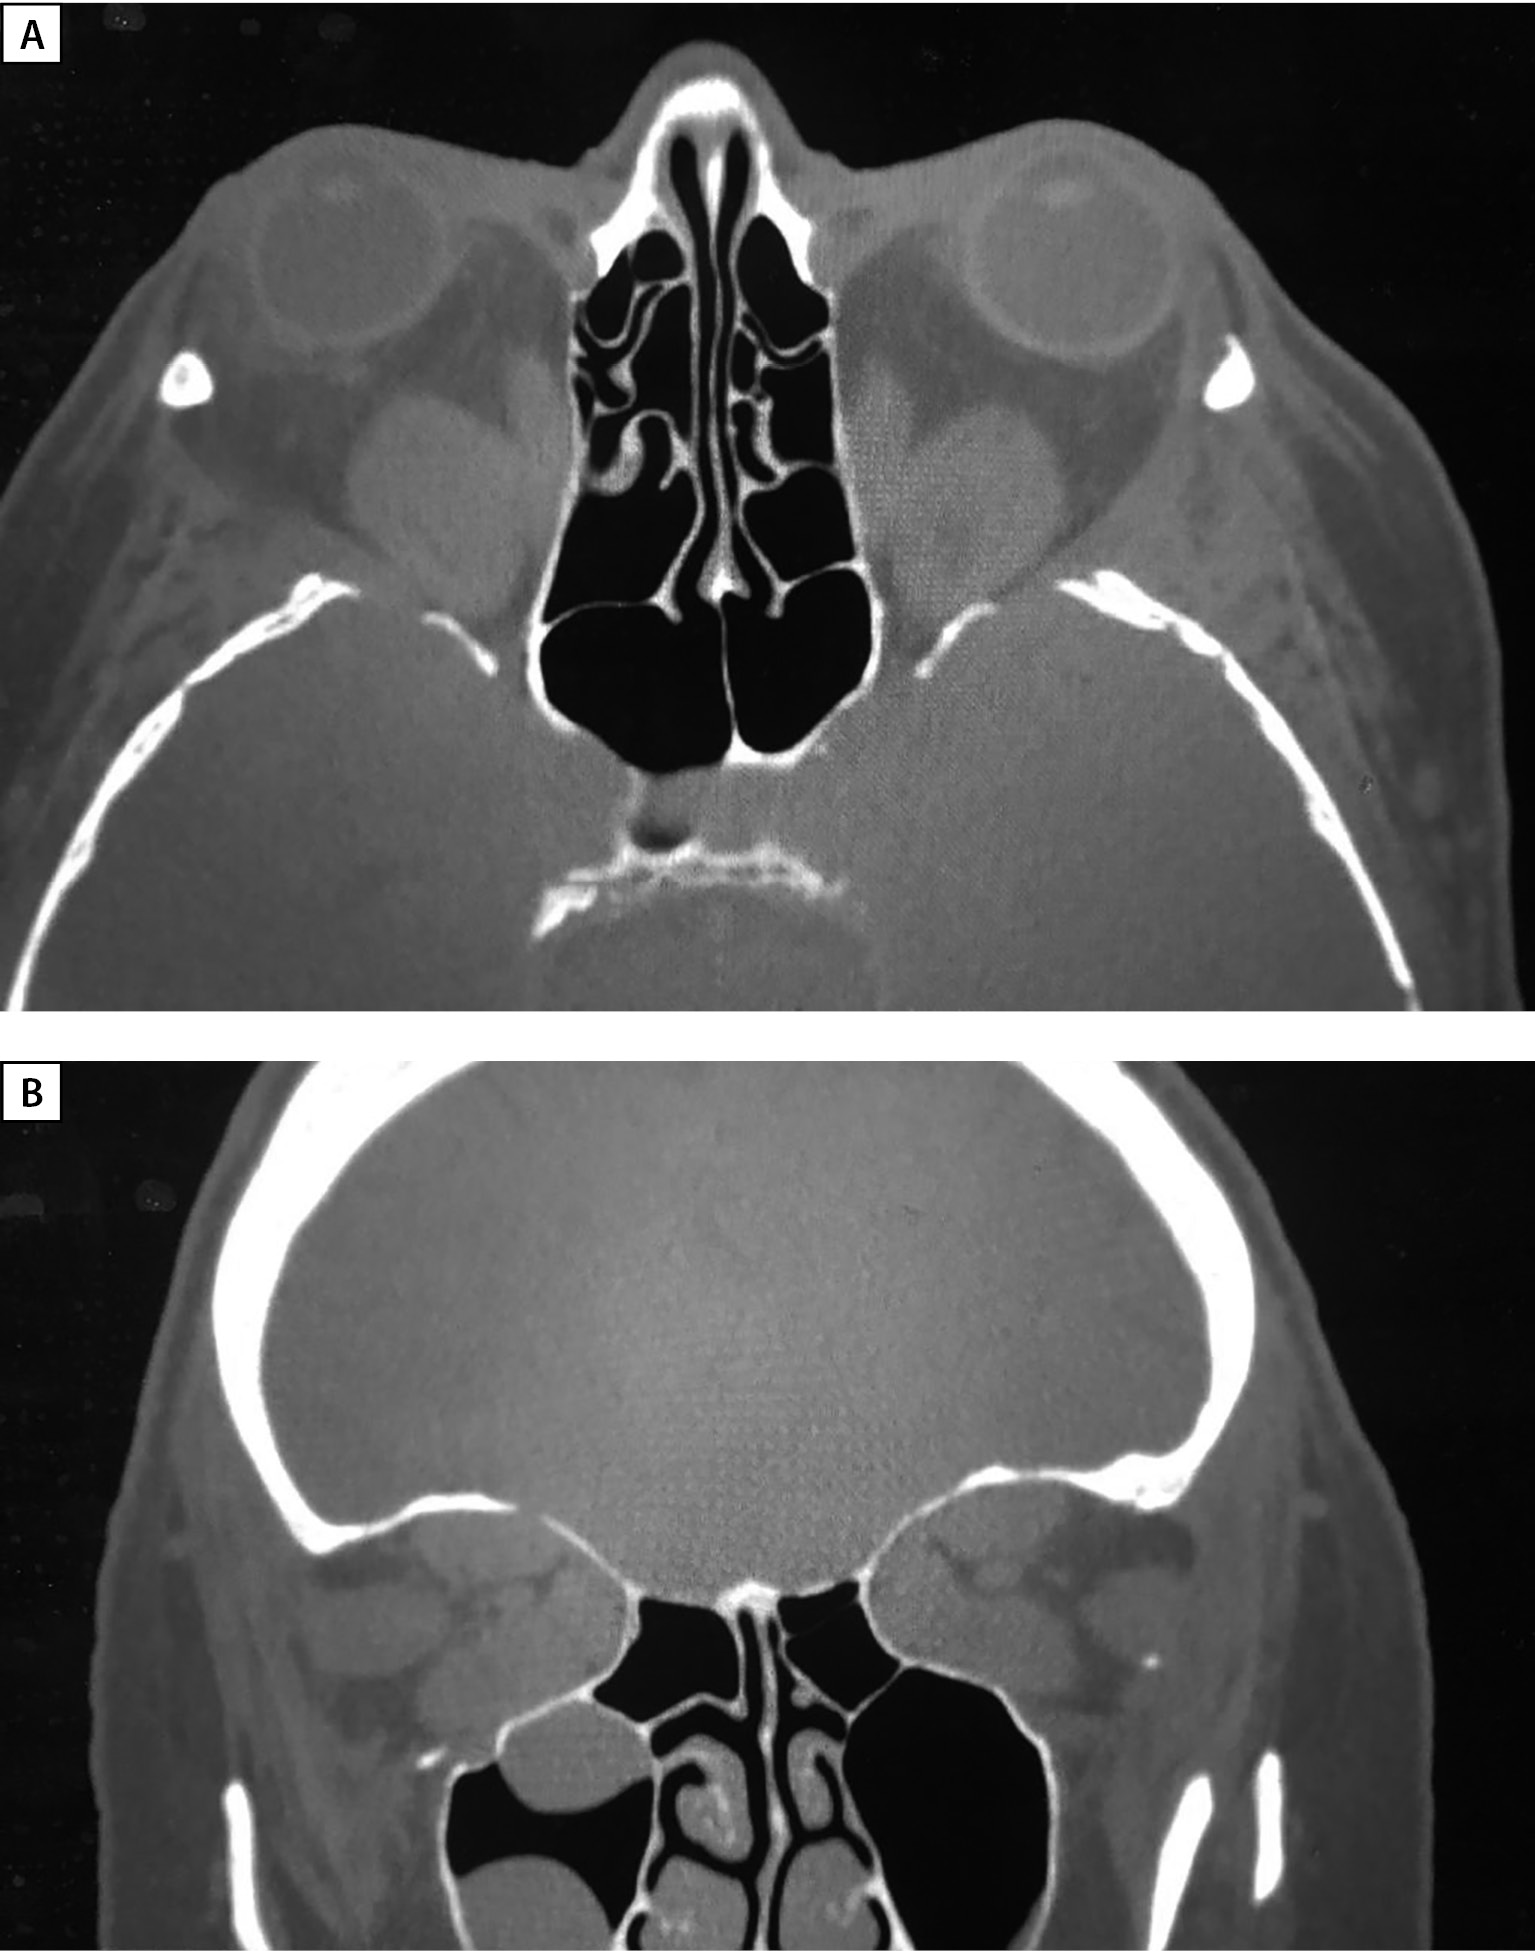

В июле 2021 г. пациентка повторно госпитализирована в ФГБУ «НМИЦ эндокринологии». По заключению офтальмолога: ЭОП тяжелой степени, активная фаза (CAS=4). ОН; частичная офтальмоплегия; ретракция век; лагофтальм (рис. 5). Состояние после пульс-терапии ГК в суммарной дозе метилпреднизолона 7750 мг + преднизолона 3600 мг (декабрь 2020 г. — март, июль 2021 г.), глубокой декомпрессии латеральной стенки обеих орбит. Острота зрения: правый глаз=0,7, левый глаз=1,0. В связи с продолжающейся активностью ЭОП (рис. 6 А, В) рекомендовано продолжить проведение пульс-терапии преднизолоном (1500 мг введено во время госпитализации) далее продолжено в амбулаторном режиме в дозе 600 мг 1 раз в неделю 4 капельницы (2400 мг).

Рисунок 6. МСКТ орбит (А — аксиальная, В — корональная проекции)

через 4 месяца после оригинальной методики глубокой латеральной КДО с двух сторон.

Определяются послеоперационные дефекты латеральных стенок орбиты,

вплоть до обнажения ТМО средних черепных ямок,

смещение наружных прямых мышц и орбитального жира

в область дефектов соответствующих стенок.